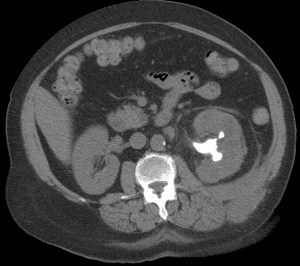

CASO 1: Paciente de 58 años que se realiza TC de abdomen tras historia de dolor abdominal y hematuria microscópica. Refiere pérdida de peso en las últimas semanas.

Estamos ante una afectación bilateral del espacio perirrenal, más evidente en el lado derecho, por masas de densidad de partes blandas en un paciente con numerosas adenopatías retroperitoneales. Estaría indicado realizar una biopsia, ya que el diagnóstico principal orienta hacia un síndrome linfoproliferativo, espcialmente linfoma no Hodgkin tipo B.

2. LINFOMA.

El linfoma renal presenta una gran variedad de manifestaciones. Entre un 3 y un 8 % de linfomas estudiados por TAC tienen afectación renal o perirrenal, más frecuentemente el tipo no Hodgkin.

Patrones de afectación del linfoma renal:

- Multiples masas renales en el riñón (+frecuente)

- Lesión solitaria.

- Adenopatías retroperitoneales con extensión directa a riñón y EPR (nuestro caso de hoy).

- Afectación del espacio perirrenal aislada.

- Infiltración difusa de uno o ambos riñones.

En el caso de que el linfoma afecte al EPR, se ve como una masa homogénea que ocupa este espacio y que desplaza el riñón hacia adelante, ocupando a menudo también el espacio pararrenal anterior. La afectación aislada del EPR por el linfoma es poco frecuente (<10%), es más común la extensión directa desde las adenopatías o grandes conglomerados/masas retroperitoneales (+frec) o la extensión desde el riñón.